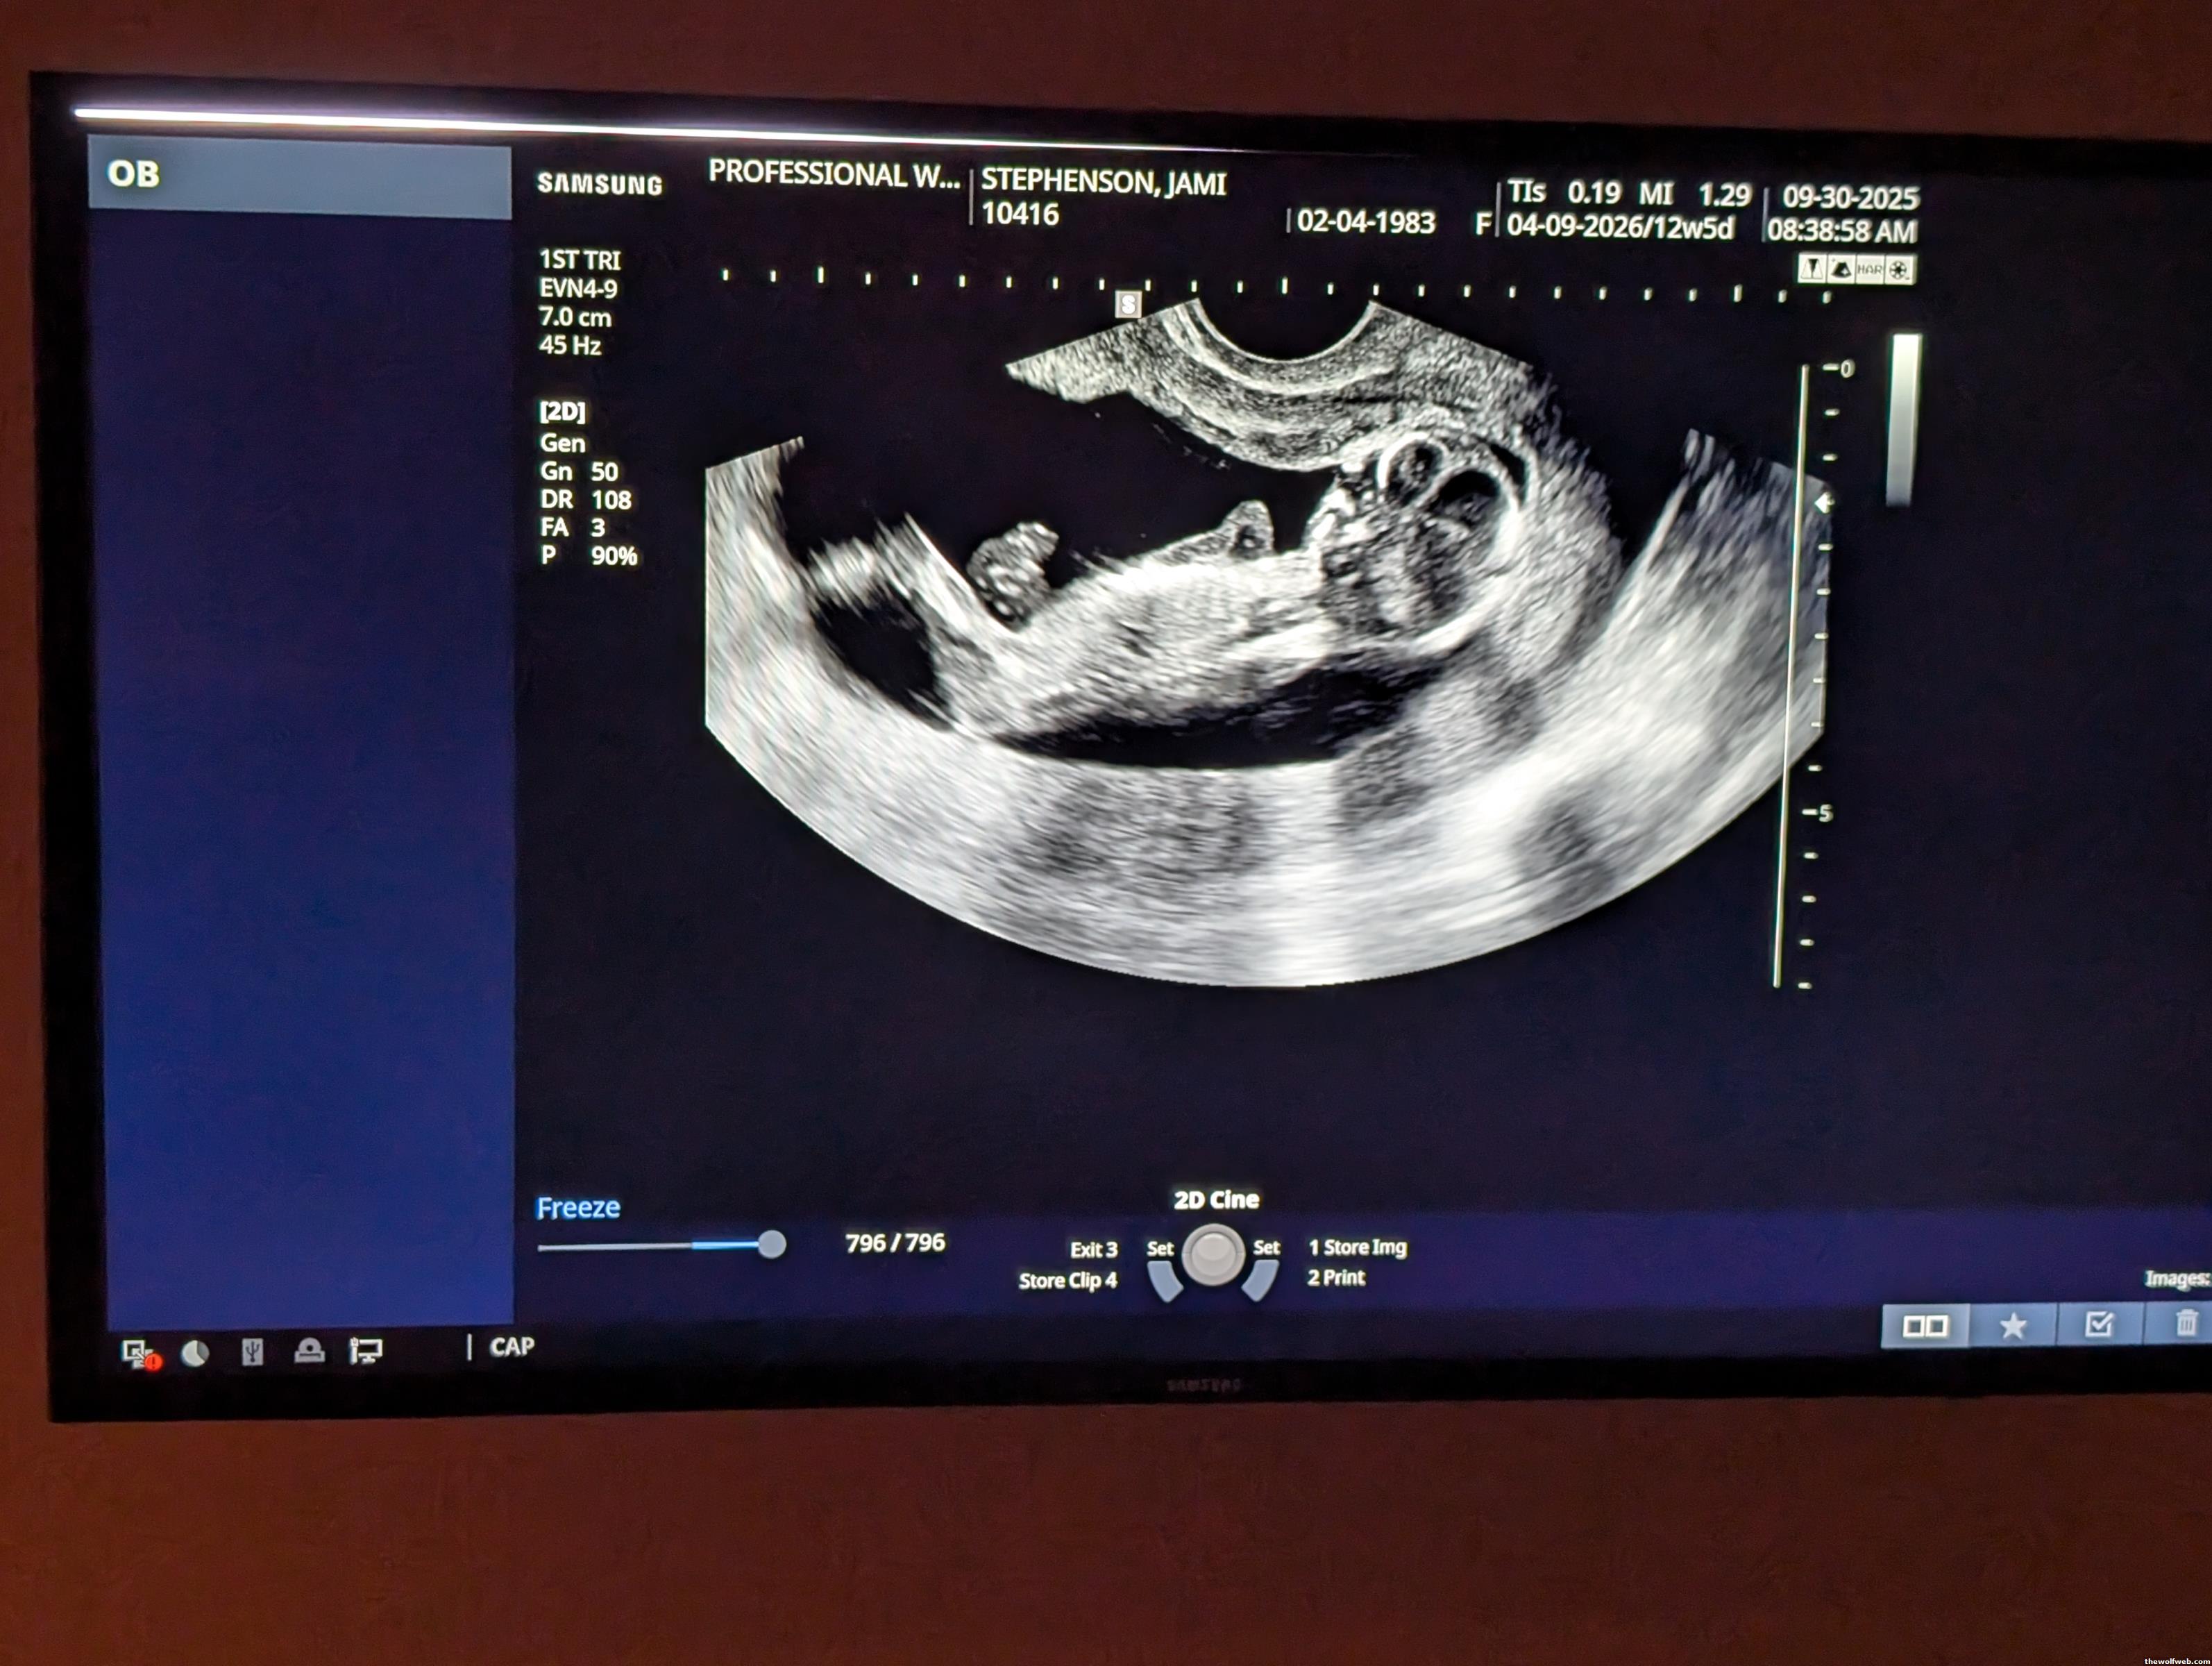

New Beginning